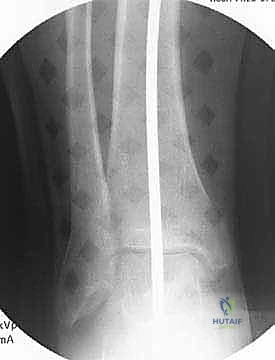

تُعد الأشعة السينية (X-rays) الممتدة من الحوض إلى الكاحل (Scanogram) ضرورية جداً لحساب زاوية التقوس بدقة وتحديد مقدار التعديل المطلوب جراحياً.

قبل العملية، يتم قياس زوايا الركبة بدقة متناهية. كل درجة من درجات التعديل يتم حسابها مسبقاً.

استخدام التخطيط الرقمي يضمن عدم حدوث تصحيح مفرط (Over-correction) أو تصحيح ناقص (Under-correction)، وهو ما يميز الجراح الخبير عن غيره.